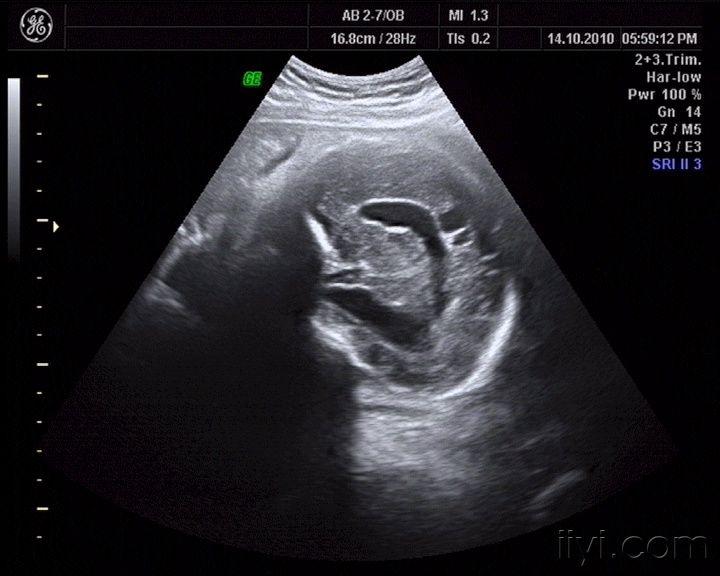

看看这个胎儿颅内情况,见过没有,考虑什么啊

图片尺寸720x576

右侧侧脑室体部上方